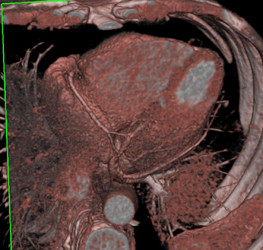

Left Main Arises Off Right Coronary Artery